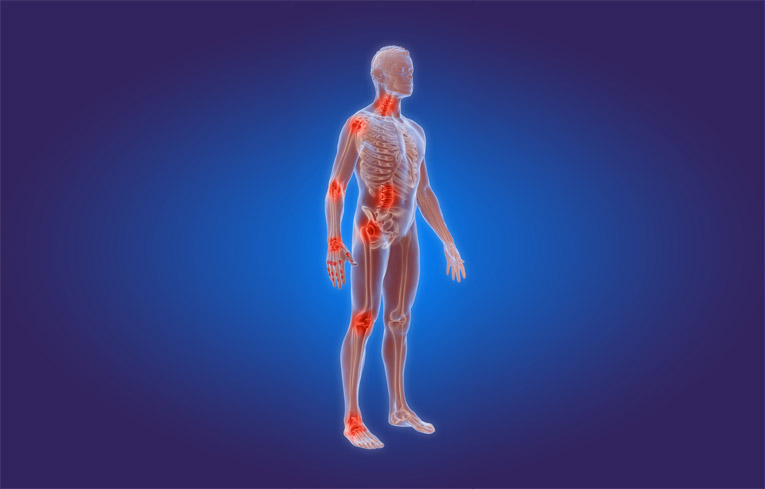

Arthritis refers to inflammation of a joint which can affect any of the important structures inside a joint, including the joint lining (synovium), bones, cartilage, or supporting tissues. Common symptoms include chronic arthritis pain, stiffness, and swelling of the joint. The condition may affect one or several joints throughout the body with knee joint pain being a common symptom. Degeneration of the cartilage can lead to destruction of the joint and the need for total joint replacement.

Psoriatic Arthritis: This type of inflammatory arthritis affects 0.3% to 1% of the population. Symptoms are present on not only joints, but also on the skin. Very similar to RA, this inflammatory arthritis has a genetic, immunologic, and environmental component. Patients develop joint pain, stiffness, and swelling along with silvery skin plaques and irritation. Often times, bones can weaken, causing joint destruction or even fusion, which can be identified on x-rays.2